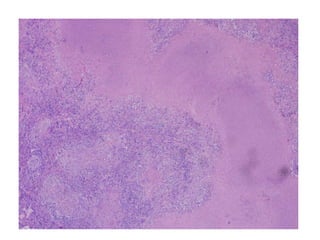

• #18 10 x Granulomatous inflammation, large thick-walled spherules contain variable sized daughter cysts ? Pyogenic reaction occurs with release of endospores from rupture of spherules ? Variable fibrocaseous granulomata, military disease, pyogenic inflammation ? Immature nonendosporulating spherules can resemble nonbudding forms of Blastomyces dermatitidis (Can Respir J 2008;15:377)

• #19 GMS Ten x

• #21 This well-formed granuloma has a large Langhans giant cell in the center. Two small spherules of Coccidioides immitis are seen within the cytoplasm of the giant cell.

• #22 Histoplasma- thin based pear shaped yeast cells Coccidomycosis- thick walled non- budding spherule 20 60 micron in diAMETER Blasto- 5- 15 micron yeast cells that divide by broad based budding . It has thick double contoured cell wall and a visible nucleus